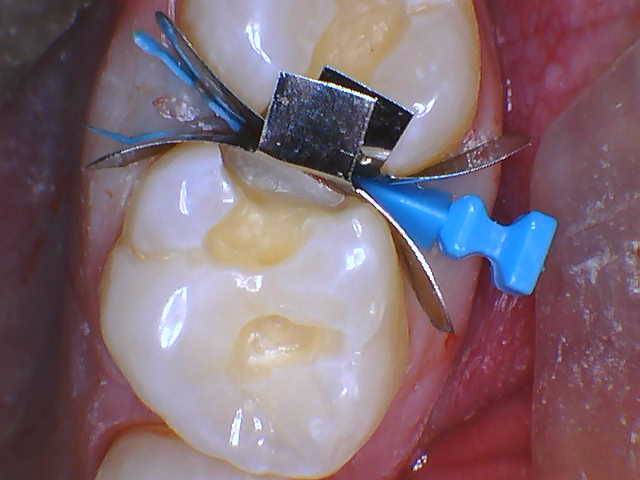

RomeneskoNick_Band and wedge 3_013025 Figure 5a

RomeneskoNick_Band and wedge 2 (2)_012325 Figure 5b

Figure 4: Prepped #2 and #3Figure 5a & Figure 5b: Wedged and banded. Garrison® Firm Bands were selected to restore back-toback to retain shape and contour and allow for burnishing to confidently form a firm interproximal contact. A small split wedge was selected as the spacing between the teeth in the box was tight. The wedge was placed so that the tips of the split wedge slide on each side of the papilla to maintain contact with the band, creating stability and a tight seal in the box when the Quad Matrix Ring is placed. It is best to place the wedge from the side of the tooth with the smaller embrasure so the wedge opens into the larger embrasure space. Typically this is from the buccal on the maxilla.